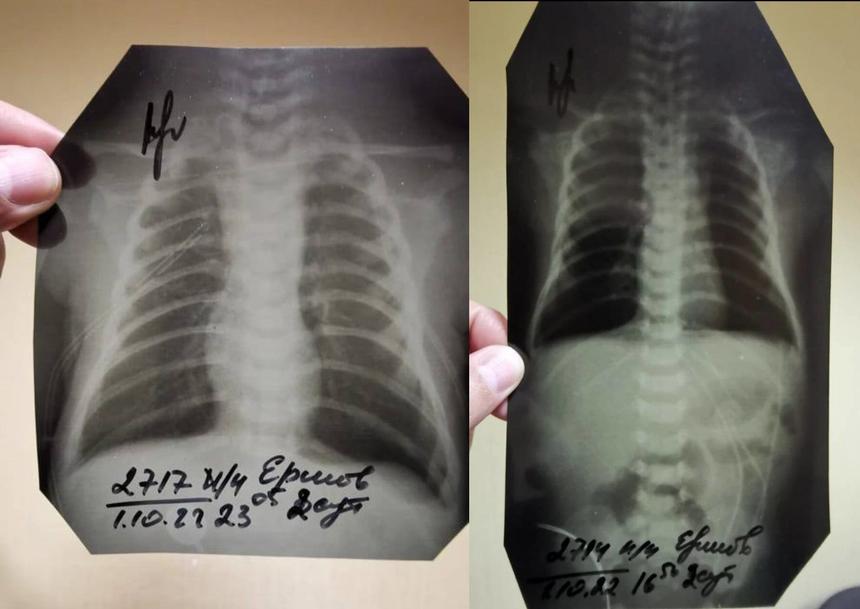

Отцу также препятствуют в ознакомлении материалов дела, заявляет сам Ершов. Странности в уликах тоже есть — например, если в прошлом году следователи говорили, что рентгеновские снимки были утеряны больницей, то после жалоб их вдруг нашли, как утверждает отец. Только есть одна деталь — место, в котором обычно аппарат печатает ФИО пациента, врача, проводившего рентген, дату и время процедуры, было вырезано на всех снимках. («Страсти» ознакомились с результатами рентгена).

«Все эти данные обрезаны. Видно, что обрезали это ножницами или чем-то ещё, криво, косо. И просто обычным маркером подписано: Ершов В. Д. Мой сын. А вместо ФИО врача, который проводил процедуру, просто стоит подпись. Интересно, что каждый снимок делался в разные дни и в разное время, а подписи стоят на всех 21 снимках одного и того же врача. Он что, один работает без выходных?», — добавил он.

Обрезанные флюорографические снимки ребенка

Ершов добавил, что подал ходатайство о запросе рабочего табеля рентгенолога, однако следствие до сих пор не удовлетворило просьбу отца ребенка.

Сам Ершов считает, что снимки, которые внезапно нашлись, на самом деле не принадлежат его ребенку.